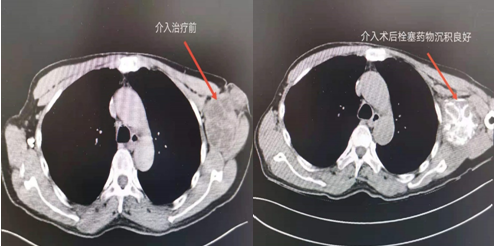

介入術(shù)前及術(shù)后CT對比圖

近日,吉林國文醫(yī)院淋巴瘤科與介入一科相互合作,成功為一例皮膚惡性黑色素瘤患者,實施了實體腫瘤動脈灌注化療栓塞術(shù),患者李某某10個月前曾確診為皮膚惡性黑色素瘤,腫瘤分布在左側(cè)腋下,患者既往曾多次行靜脈化療及免疫治療,但腫瘤病情仍然繼續(xù)進展,患者目前左側(cè)腋下腫瘤病灶增長較快,伴有局部脹痛感,淋巴瘤科左淑波主任綜合分析患者病情后,邀請介入一科韓長清主任進行共同商討治療方案,評估是否可行介入手術(shù)治療,經(jīng)兩位主任共同商討后決定,可給予患者行腫瘤供血動脈化療栓塞術(shù)介入治療。介入術(shù)中非常順利,成功尋找到腫瘤供血動脈并給予治療,術(shù)后患者恢復(fù)良好,疼痛癥狀有所改善。